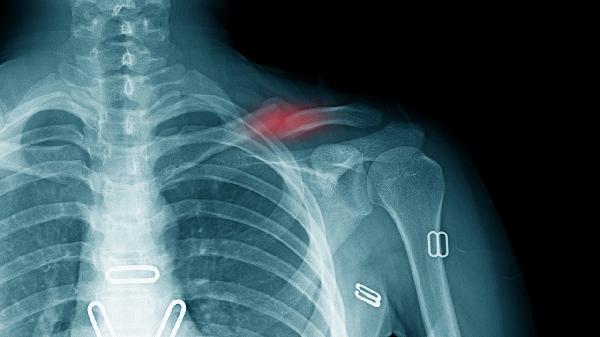

肩膀锁骨骨折可通过手法复位、支具固定、药物治疗、物理治疗、手术治疗等方式治疗。肩膀锁骨骨折通常由直接暴力、间接暴力、骨质疏松、运动损伤、交通事故等原因引起。

适用于无明显移位的锁骨骨折。医生通过专业手法将错位的骨折端重新对齐,恢复骨骼正常解剖位置。复位后需配合外固定装置维持稳定性,过程中需避免剧烈活动以防二次损伤。复位后2周内需定期复查X光片评估愈合情况。

适用于开放性骨折、严重移位或合并血管神经损伤的情况。常用术式包括钢板螺钉内固定、髓内钉固定等。术后需配合抗生素预防感染,早期开始被动关节活动。内固定物通常需1-2年后根据愈合情况决定是否取出。